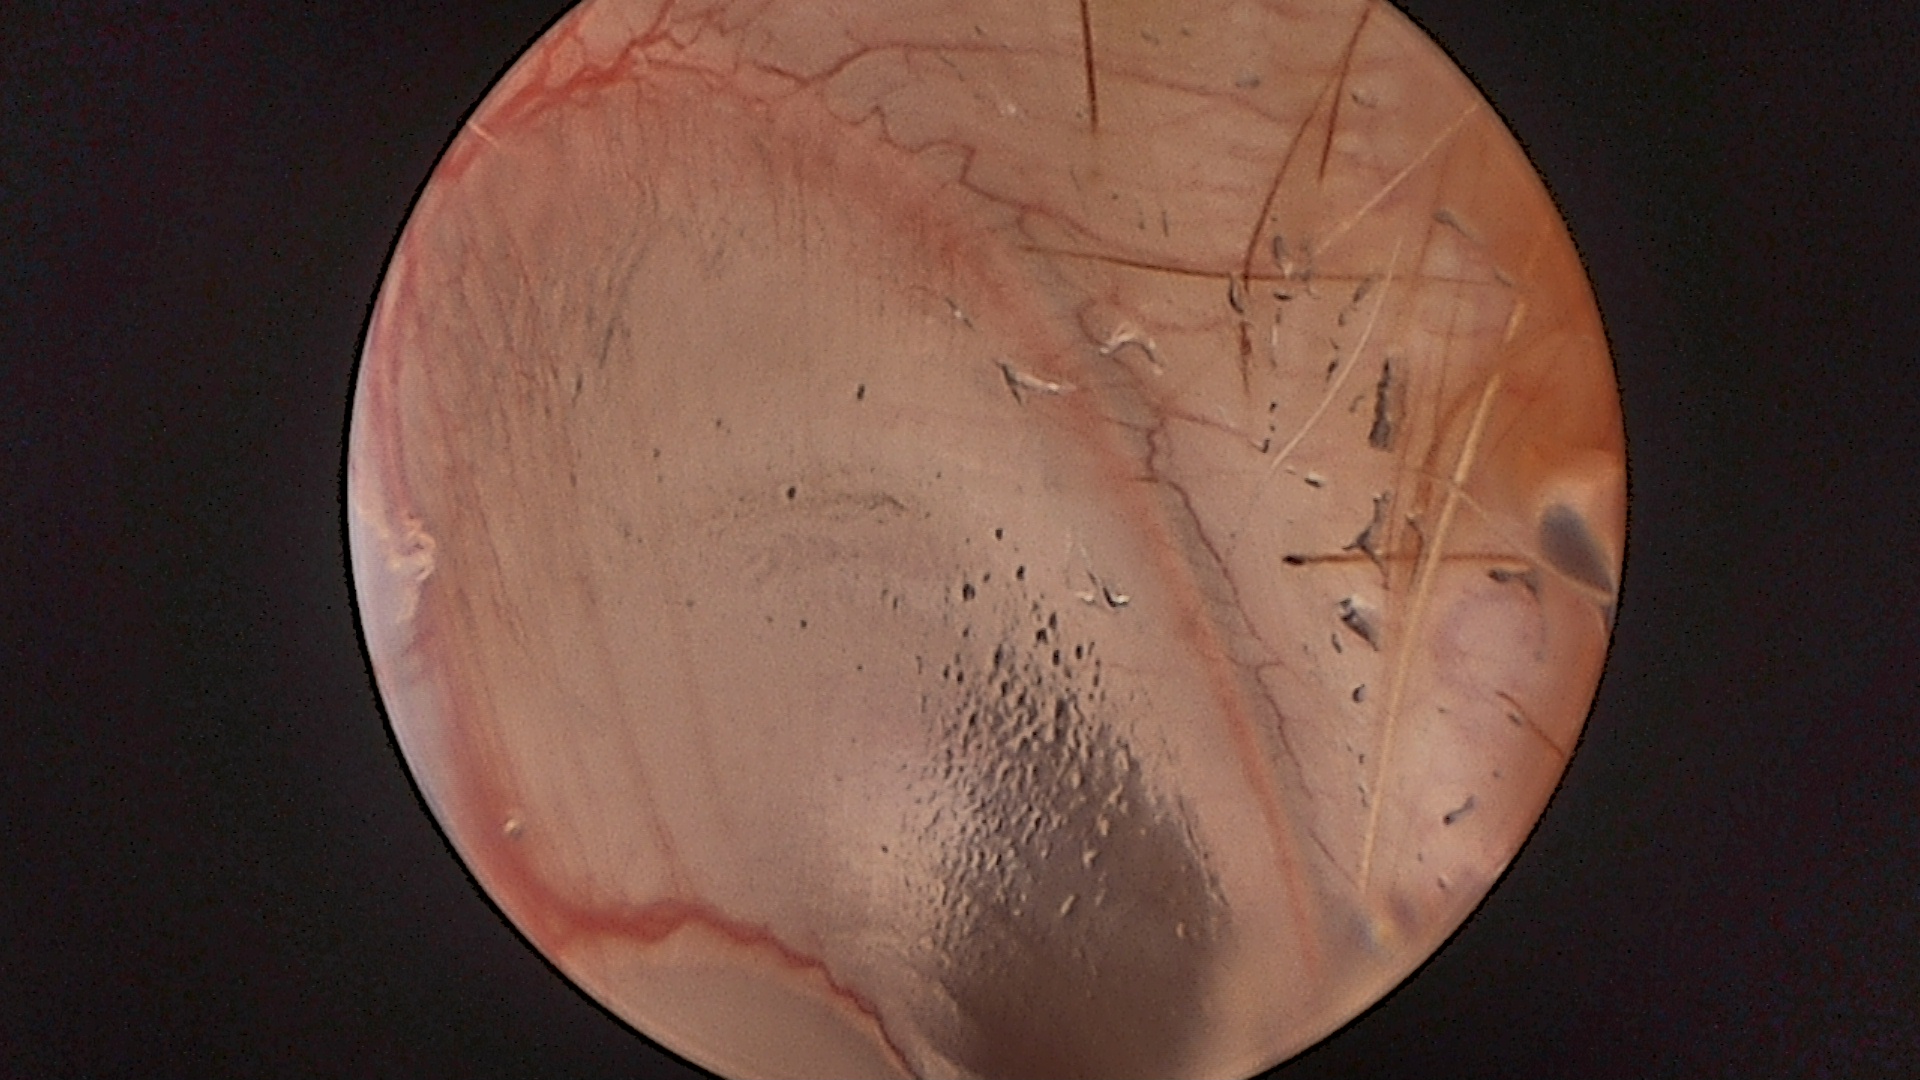

Ohr (Otoskopie):

Die Otoskopie bringt völlig neue Möglichkeiten zur Behandlung von Ohrenentzündungen. Hier ein Video zur Otoskopie